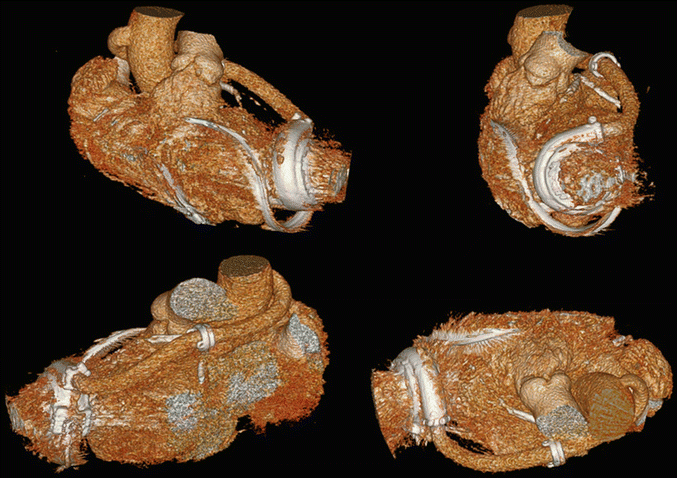

Fig. 27.3

HVAD outflow graft tunneling through the transverse sinus by 3D computed tomography (CT) scan reconstruction